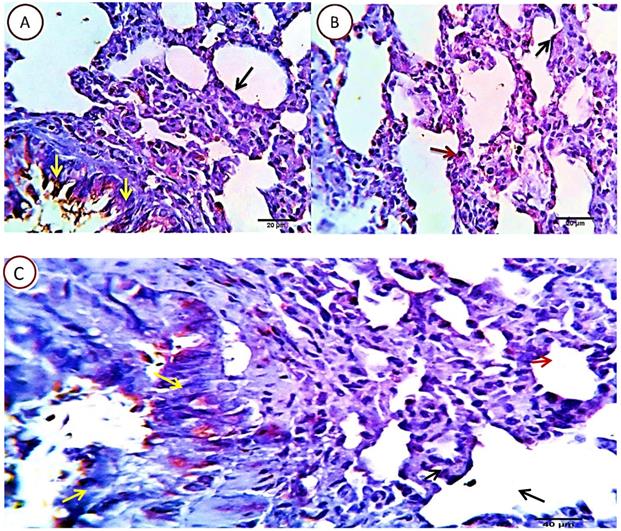

Serial sections from lungs of this group pointed out a dramatic apoptotic changes in all of the pulmonary histologic structures as the bronchial epithelium, alveolar cells of pneumocytes type 1 and 2 beside the alveolar macrophages, all were affected with a mild to moderate proportional numbers 27-30% HPF (average 28.8%) of the morphometric analyzed cells, they were positively reactive to caspase -3, with the more pronounced effect in the alveolar macrophages and pneunocytes type 2, postulating an additional immune-depressive effect of the cyclophosphamide beside its real cytotoxic effect (Fig. 7).

Figure 7

Photomicrograph from lung of Cyclophosphamide treated group, immune-stained with Caspase-3, showing mild to moderate proportional numbers (27-30 %) of cells positively reactive to caspase-3, with the more pronounced effect in the alveolar macrophages (red arrows) and pneunocytes type 2 (green arrows). Pneumocytes type 1 (black arrow) and some bronchogenic cells (relative and un-relative) are also positively stained. Scale bars 20, 30 um.

Group 3: Cyclophosphamide and Quercetin

Serial sections from lungs of this group pointed out an optimizing protective effect of the used quercetin as the apoptotic index in most of the pulmonary tissue was very low. Nearly, 5-7% HPF (average 7%) of the morphometrically analysed cells were positively reacted, with the pneumocytes type 2 as the most affected cells, they were seen related to the alveolar wall and the interalveolar tissue. Other cells including bronchial, bronchiolar and alveolar cells (pneumocytes type 1) were normal or sparsely affected, especially the unrelated positively stained bronchial epithelial cells (Fig. 8).

Figure 8

Photomicrograph from lung of (Cyclophosphamide and Quercetin) immune-stained with Caspase-3, showing very low (5-7%) of the cells are positively stained. The pneumocytes type 2 are the most affected cells, they are seen related to the alveolar wall (red arrow) and the interalveolar tissue. Other cells including bronchial (yellow arrows), bronchiolar and alveolar cells (pneumocytes type 1) (black arrow) appears normal or sparsely affected, especially the unrelated positively stained bronchial epithelial cells (yellow arrows). Scale bars 20, 40 um.

On the other hand the present study investigated the therapeutic effect of quercetin on cyclophosphamide induced lung damage and evaluated the parameters of immuno and histopathological examinations. Examination of lung tissues in the cyclophosphamide treated group suggested a dramatic apoptosis of bronchial epithelium, alveolar cells of pneumocytes type 1 and 2 beside the alveolar macrophages, all were affected with a mild to moderate proportional numbers 27-30% HPF (average 28.8%) of the morphometric analyzed cells were positively reactive to caspase-3 enzyme, with the more pronounced effect in the alveolar macrophages and pneumocytes type 2, postulating an additional immune-depressive effect of the cyclophosphamide beside its real cytotoxic effect. On the other hand, an optimizing protective effect was observed in quercetin treated rats as the apoptotic index in most of the pulmonary tissue was very low. The anti-inflammatory impact of QUE causes inhibition of inflammatory mediators and affects immunity and the inflammation response.